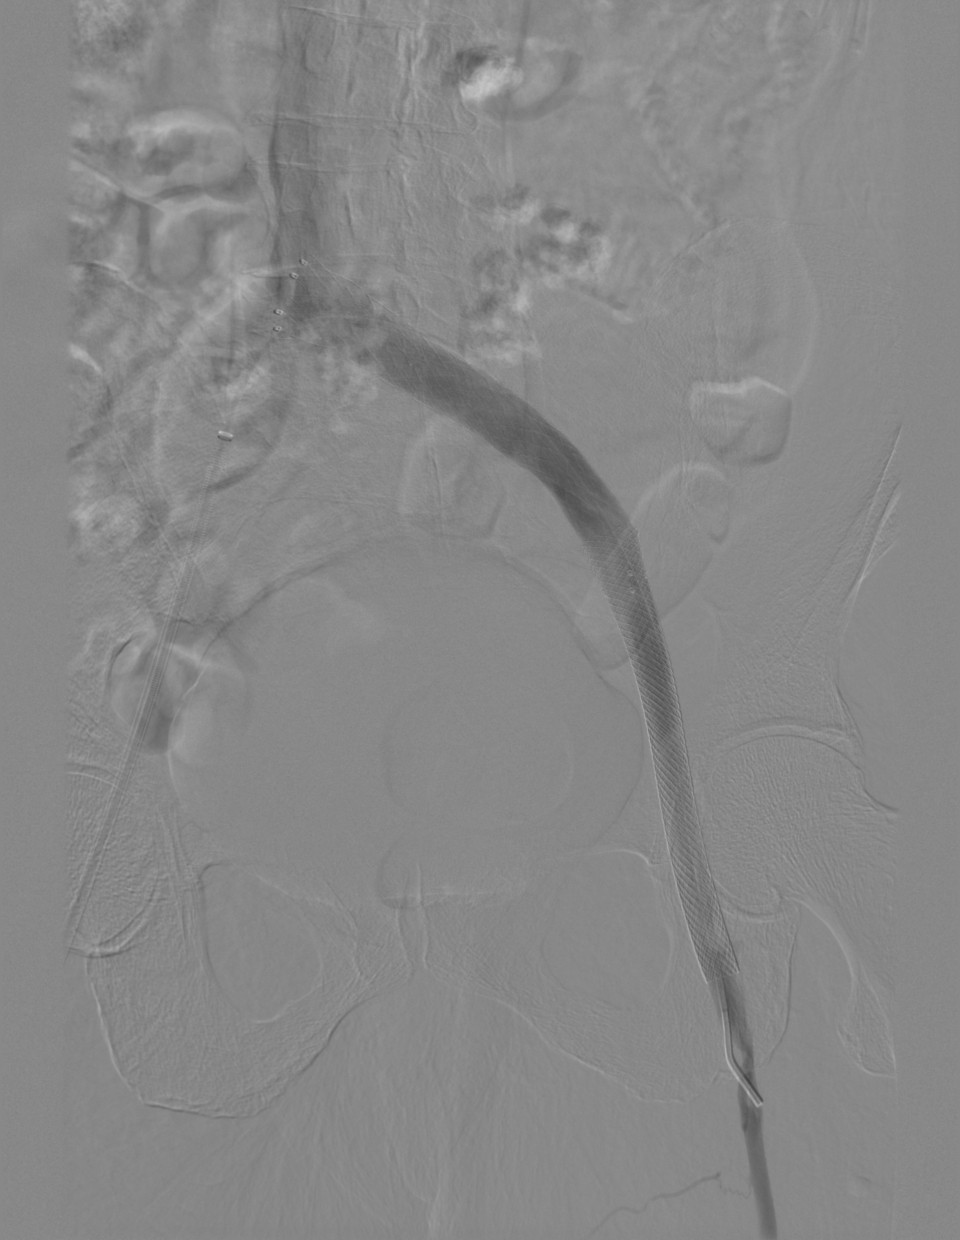

門靜脈高壓治療

tips手術(shù)治療前

tips手術(shù)治療后

有效降低門靜脈壓力,降低消化道出血及腹水等相關(guān)并發(fā)癥,本技術(shù)省內(nèi)領(lǐng)先。